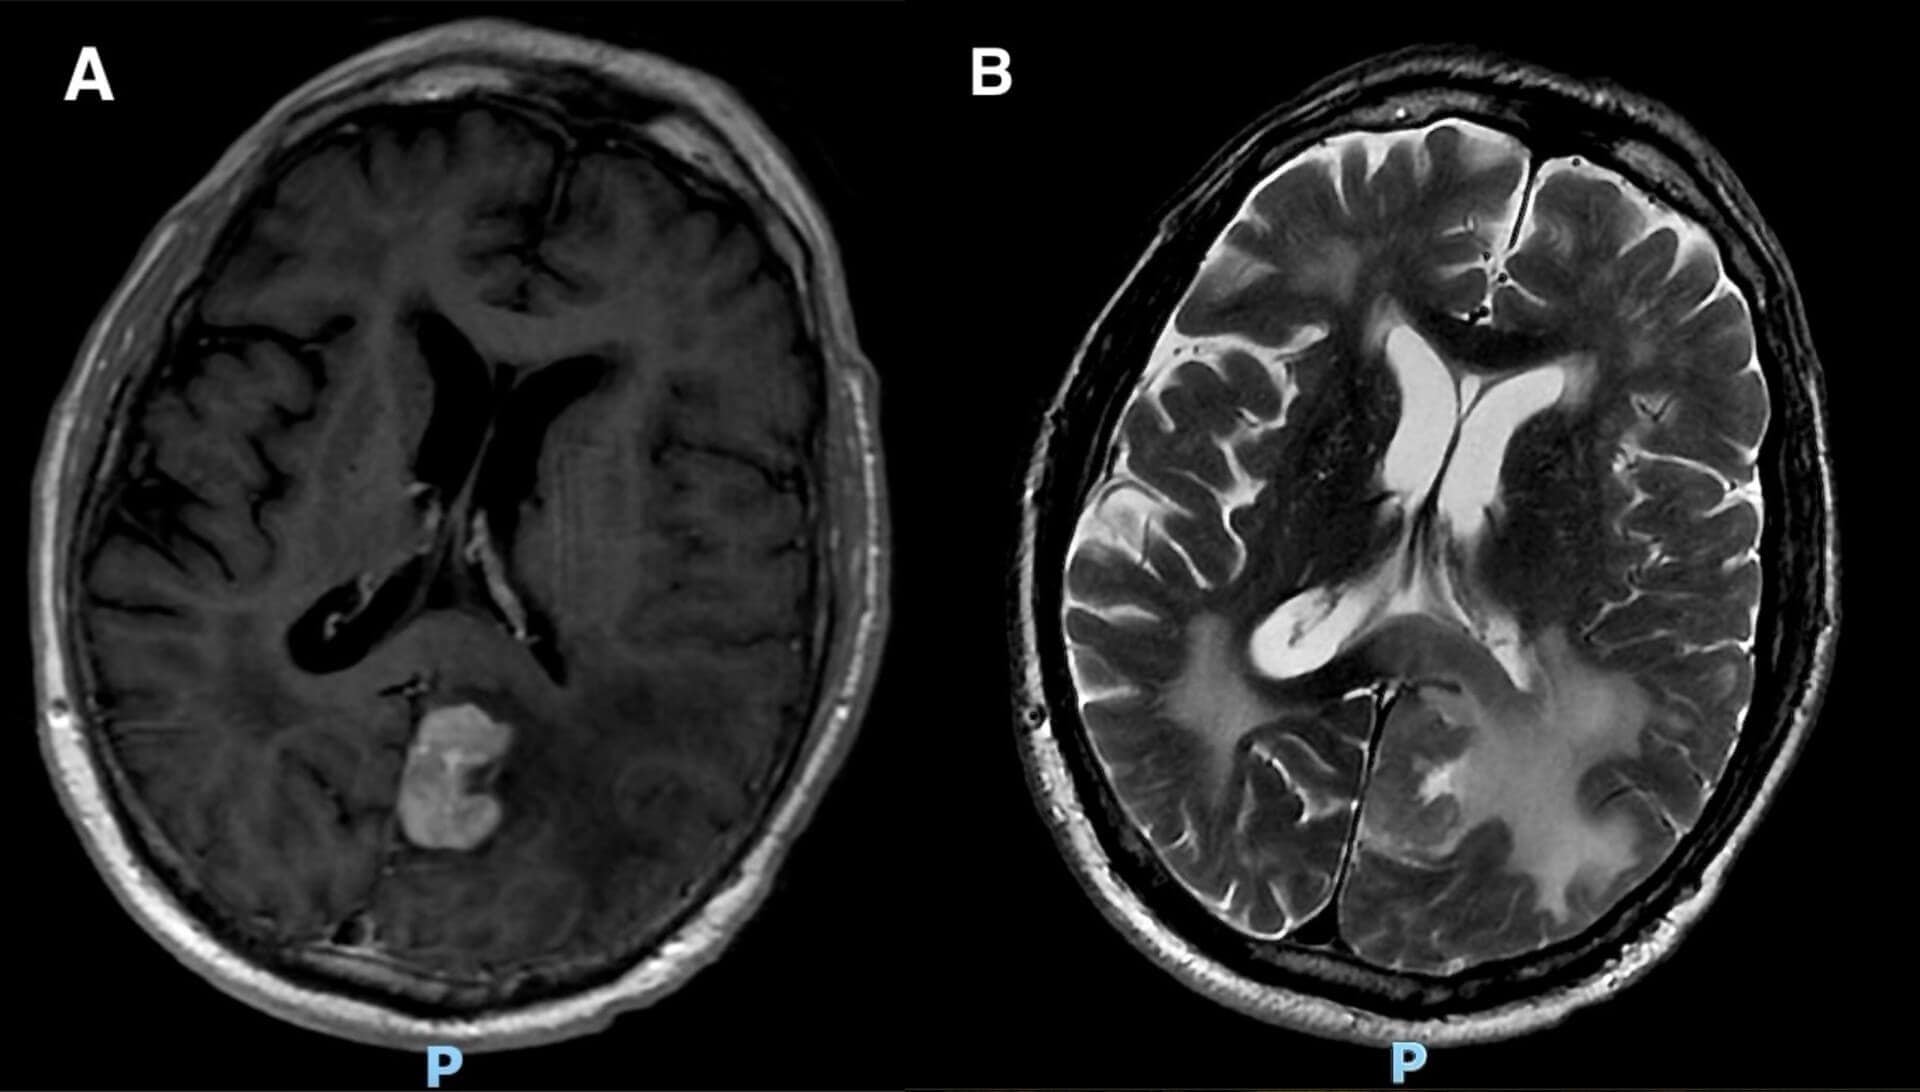

Optometry examination was performed on post-op day one following brain lesion biopsy. The patient was notably confused during the exam but was oriented to person (could identify self but not place or time during the visit). Visual acuity was 20/20 in each eye. Pupil and extraocular motility evaluation were normal. Color vision evaluation was attempted, but the patient was unable to perform this test due to confusion. Slit lamp examination, intraocular pressure, and dilated fundus examination were all within normal limits; there were optic disc abnormalities or retinal/choroidal lesions. Automated perimetry (Humphrey Visual Field 24-2) was performed and demonstrated a significant right homonymous hemianopia (Figure 2).

Figure 2. Serial Humphrey visual field (HVF) examinations on post-op day #1 (POD#1), and post-op months 1 and 4 (POM#1, POM#4).

The patient’s oncology team initiated high-dose methotrexate-based chemotherapy and continued systemic steroids. Management was later transitioned to ibrutinib, a Bruton’s tyrosine kinase (BTK) inhibitor chemotherapeutic agent. Systemic evaluation, including positron emission tomography (PET) imaging, demonstrated no findings that would indicate extracranial lymphomatous involvement (i.e. the patient’s disease seemed to be confined to the brain). The patient’s level of confusion improved to some degree. At follow-up eye exams 1-4 months after neurosurgical resection, the visual field testing demonstrated remarkable recovery of the patient’s right homonymous hemianopia (Figure 2).